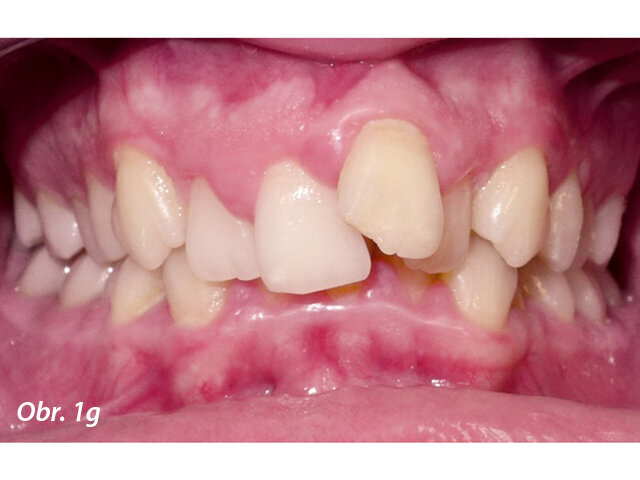

17letý chlapec přišel na konzultaci v prosinci 2014. Při intraorálním vyšetření bylo zjištěno: vztah molárů v I. třídě dle Anglea oboustranně a vztah špičáků v I. třídě vlevo a II. třídě vpravo. Šířka horního zubního oblouku v úrovni molárů byla normální, v místě premolárů však byl zubní oblouk výrazně zúžený a v mezišpičákové oblasti bylo výrazné stěsnání. V dolním zubním oblouku (úzký, tvar paraboly) bylo stěsnání s úplným deficitem místa pro zub 42, který byl v ektopické lingvální poloze. Hloubka skusu byla stoprocentní s traumatickým nákusem do gingivy v okolí dolních frontálních zubů. Zuby horního oblouku byly mírně větší než průměr, s malým nepoměrem Boltonova indexu. Objektivní extraorální vyšetření odhalilo syndrom dlouhého obličeje, vývoj střední třetiny obličeje byl normální a nazální pyramida byla široká ve spojení s mírnou mandibulární retruzí (obr. 1a–h).